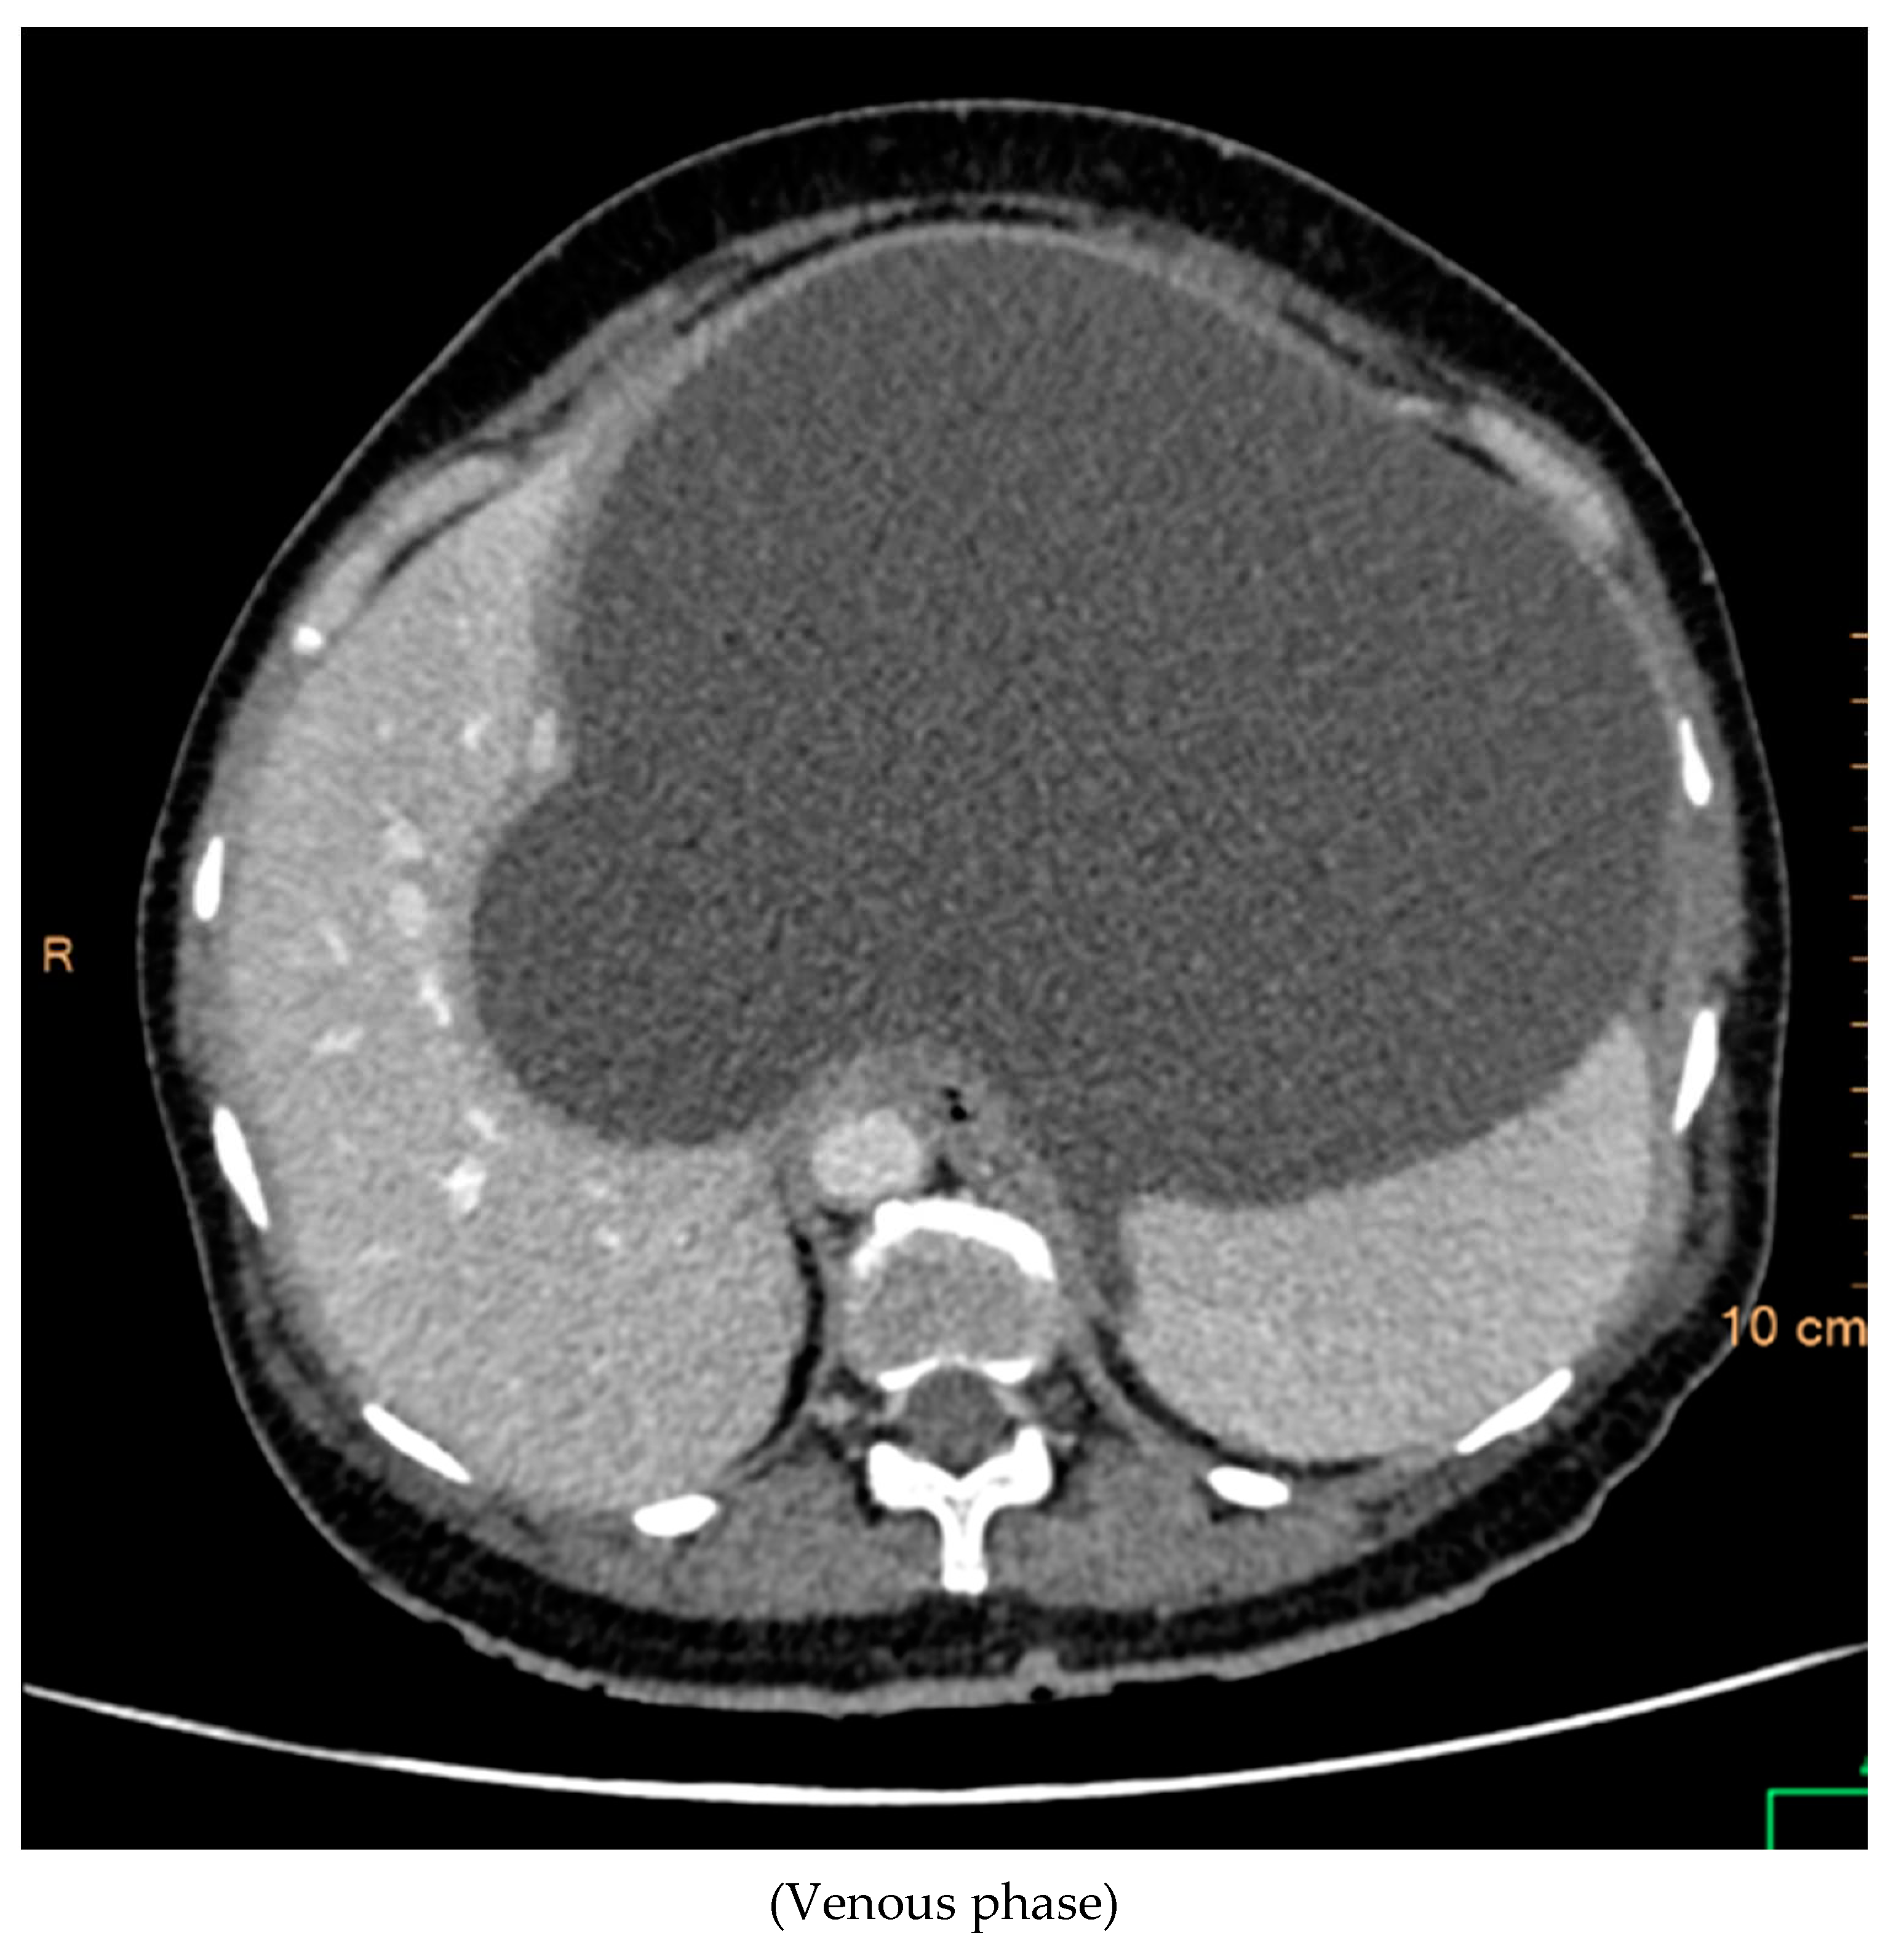

CT Contrast Abdomen Findings

The contrast-enhanced computed tomography (CT) findings reveal a series of notable features within the abdominal region. Multiple well-defined peripherally enhancing cystic lesions, each exhibiting internal septations, are observed in distinct locations, including the epigastric, gastrohepatic, left lumbar, and greater omentum regions along the greater curvature of the stomach. These cystic formations present as significant entities in the imaging, demonstrating a complex architecture.

Preprints 94567 g003

A large, well-defined peripherally enhancing cystic lesion with several internal enhancing septations is identified in the epigastric and gastrohepatic region. There is a possibility that this lesion originates from the left lobe of the liver. Notably, the superior extension of this lesion reaches up to the left hypochondriac and subdiaphragmatic regions. Laterally, it extends towards the left lateral abdominal wall, exerting pressure and indentation on the right lobe of the liver.

Inferiorly, the large cystic lesion exerts compression on the body of the stomach, causing displacement. Posteriorly, the lesion notably compresses the body of the pancreas. Further examination reveals compression on the common hepatic artery, portal vein, and splenic vein at the splenoportal junction, although these vessels remain patent. Anteriorly, the lesion extends up to the anterior abdominal wall, showcasing its expansive nature.

The posterior and left lateral aspects of the lesion result in the displacement and compression of the mid and upper pole of the spleen. Additionally, collateral vessels are observed in the perisplenic and left hypochondriac regions, indicating the potential impact of this cystic lesion on vascular dynamics. The comprehensive CT contrast findings provide valuable insights into the intricate anatomical alterations and potential clinical implications associated with these cystic lesions within the abdominal cavity.

Preprints 94567 g004

Preprints 94567 g005